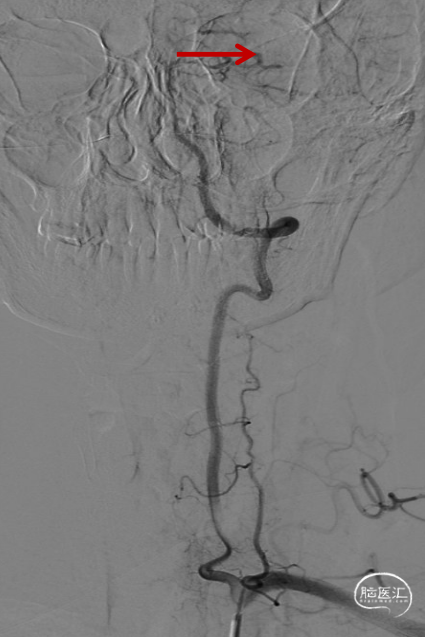

等待10分钟,复查造影颈内动脉及远端分支通畅,结束手术。DynaCT左侧外囊区域少许造影剂渗出。

术后4h复查CT示渗出消失,左侧额叶导叶低密度灶。

术后第三天MRI示左侧额叶及导叶梗死,MRA血流通畅。患者症状明显缓解,NIHSS评分2分。